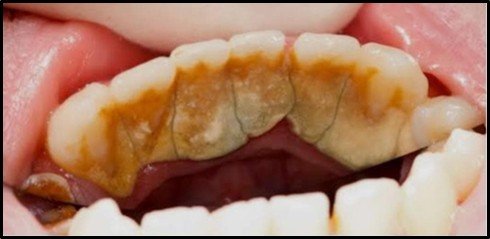

At Trail Dental, our dental scaling procedure stands out as a safe, effective, and painless solution to maintaining your oral health. This routine treatment focuses on removing plaque, tartar, and surface stains from your teeth, ensuring a cleaner, brighter smile. What sets scaling apart is its ability to address areas below the gumline, preventing long-term issues such as gum disease, bad breath, and even tooth loss. It’s more than just cleaning—it’s an investment in the health of your mouth.

We believe in merging modern dental technology with compassionate care to create a pleasant experience for our patients. Using advanced ultrasonic tools, our dental experts deliver a thorough yet gentle cleaning process. These tools allow us to effectively target buildup without causing discomfort, ensuring your visit is as smooth as possible. For patients experiencing gum-related issues, we also offer deep scaling, known as root planing, to support healing and strengthen gum health.